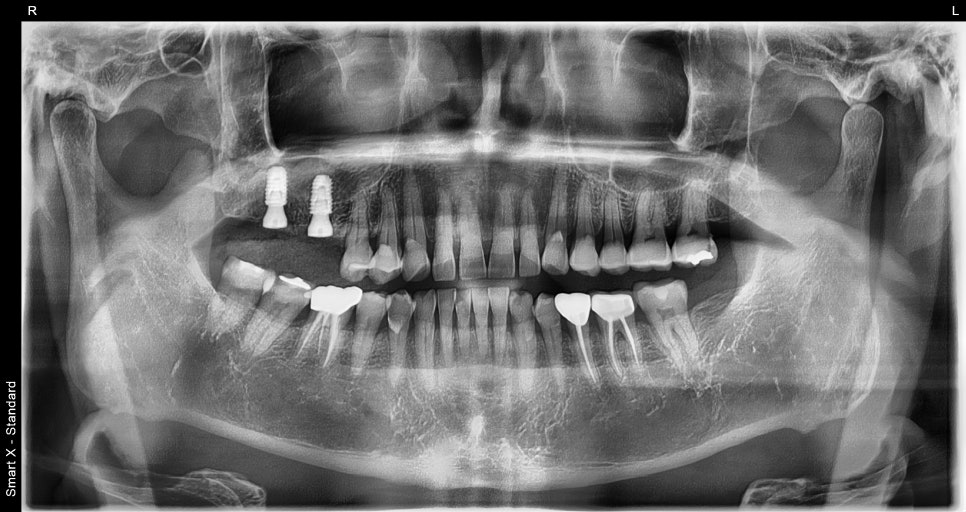

이후 약 2~3개월 간 잇몸뼈가 안정되는 기간을 거쳤고,

체크 내원 시 파노라마 검사에서

임플란트가 잘 자리 잡고 있는 것을 확인했습니다.